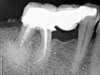

Le kyste est éliminé par une voie latérale dite "chirurgie à rétro".

La racine ré obturée est rebouchée par dessous.

Un matériaux de comblement est placé dans l'espace laissé libre.

4 mois après un bridge est refait sur une dent sauvée.